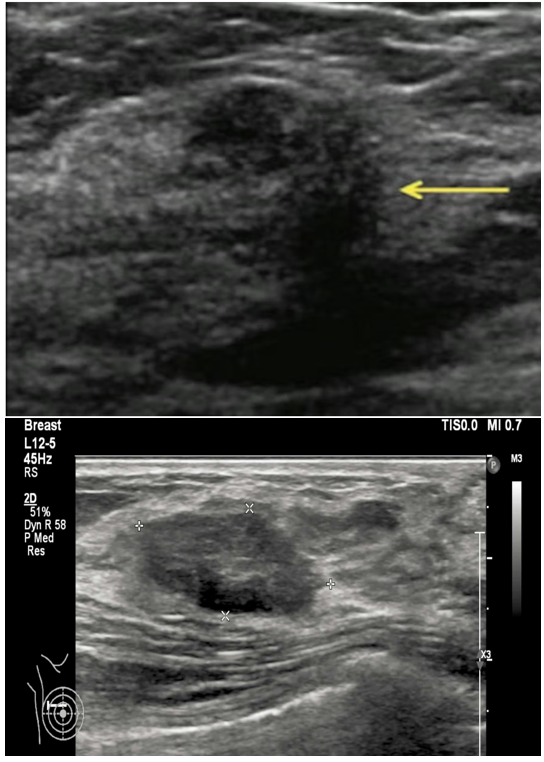

An Ultrasound Mammogram is a radiation-free imaging test that uses high-frequency sound waves to examine breast tissue. It helps doctors evaluate breast lumps, pain, swelling, or other abnormalities and is especially useful for women with dense breast tissue.

Differentiate between solid masses and fluid-filled cysts